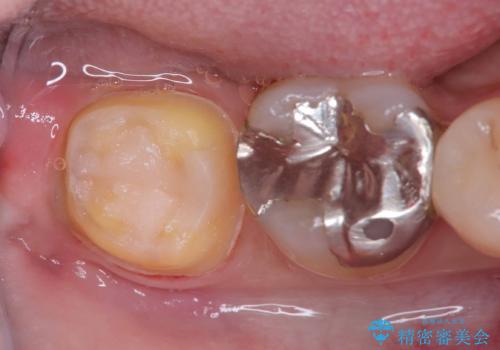

- 銀歯と歯の間に穴があり虫歯になっていました。

銀歯と虫歯を除去後、オールセラミッククラウンで治療を行いました。

銀歯のほとんどは錆びる金属で出来ています。

銀歯を外すと大小様々ですが、そのほとんどが虫歯になっていることが多いです。

今回も虫歯は大きく神経の近くまで広がっていましたが、神経は取らずに治療を終えることが出来ました。